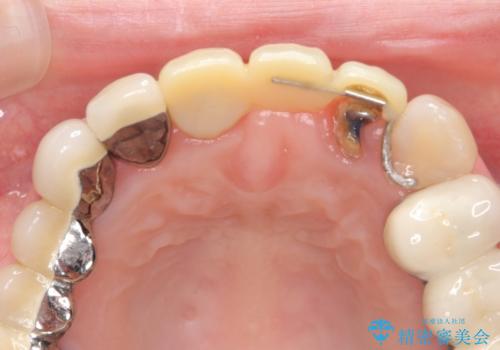

前歯ブリッジのやりかえ

- 前歯の審美障害、見た目の改善を希望され来院されました。

歯肉縁下カリエスも認められるため、挺出を行いセラミックブリッジを審美的に新製します。

- 47万円(仮歯×3・ファイバーコア×2・ジルコニアクラウン×3 歯の挺出)費用は治療当時の料金となります